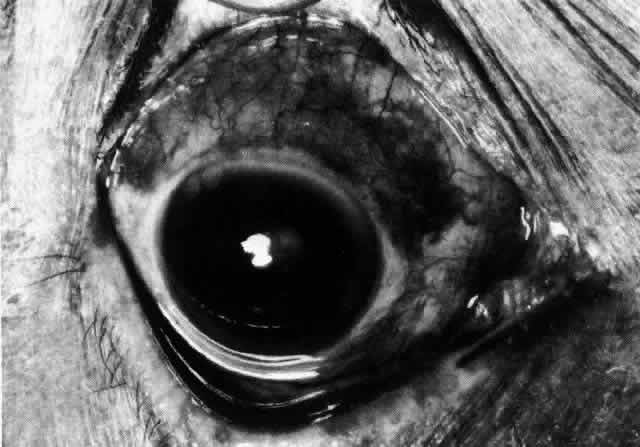

Diffuse Anterior Scleritis Diffuse anterior scleritis is the most common and least severe type of scleritis. The inflammation is widespread, and it may involve either a small segment or the whole of the anterior segment, sometimes with such severe overlying inflammation as to justify the name “brawny” scleritis (Fig. 29). On slit lamp examination, the vascular pattern of both deep and superficial layers may be distorted, so that the normal radial pattern of the vessels is lost; large anastomotic channels develop, leading to beading and tortuosity of the remaining vessels (Figs. 30 and 31; Color Plate 1C).

In this relatively benign form of scleral inflammation, the fluorescein angiogram reveals a rapid flow pattern in which the transit time of the dye is very rapid (as in episcleritis) (Figs. 32 and 33). Subtle changes occur in the capillary network, and abnormal leaking vessels appear after prolonged inflammation. These changes do not disappear after the inflammation subsides or is treated (see Fig. 31).